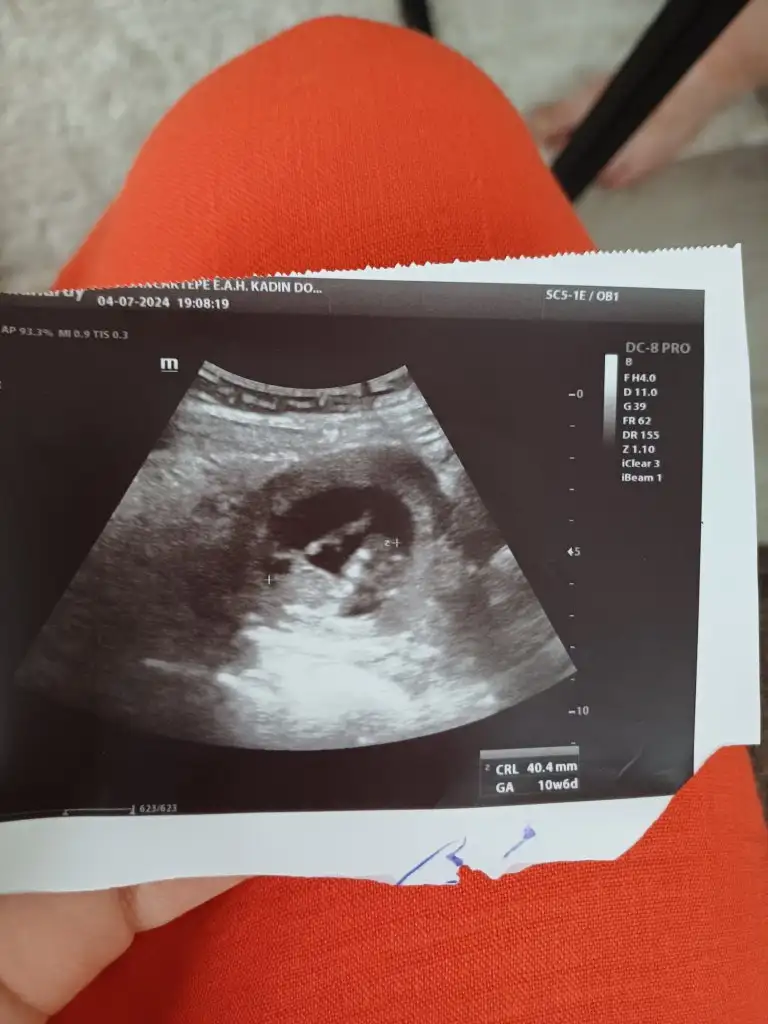

Görüntü çok net değil ama bende tahmin alabilir miyim günüyle uyumlu 10+6

Yaaa kızlar ne güzel cinsiyetler öğrenilmeye başlanmış 😍😍 herkesin gönlündeki olsun inşallah ama önce sapsağlıklı olsun bebişlerimiz.. dün 10+5 de doktor bize yorum yapmadı. 12+0 da detaylı ultrason bakacağım o zaman bir tahmin yaparız dedi 🤭🤭 ama varsa bir yorumunuz yazabilirsiniz bize de 🤗